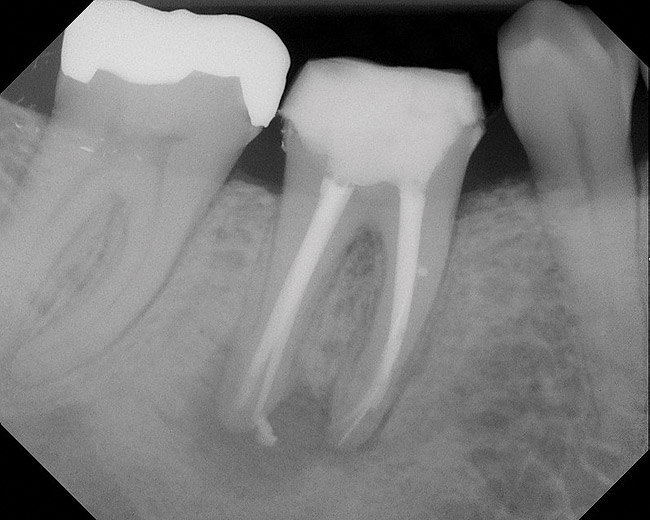

Figure 5  Retreatment of the case shown in Figure 4.

Figure 5